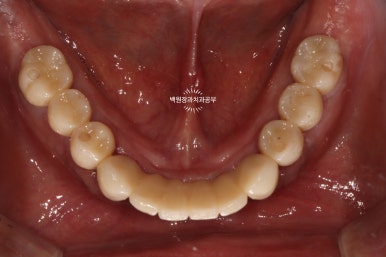

그리고 임시치아를 붙여드렸습니다.

사실 임시치아라 치아 모양도 둥글둥글하고 색깔도 예쁘지 않습니다.

그리고 임시 치아 사이에 간격도 존재하구요.

정면에서 보시면 임시 치아와 다르게 훨씬 깊이감 있는 색상으로 제작되어 자연스럽고, 완성도 있는 형태를 확인하실 수 있습니다.